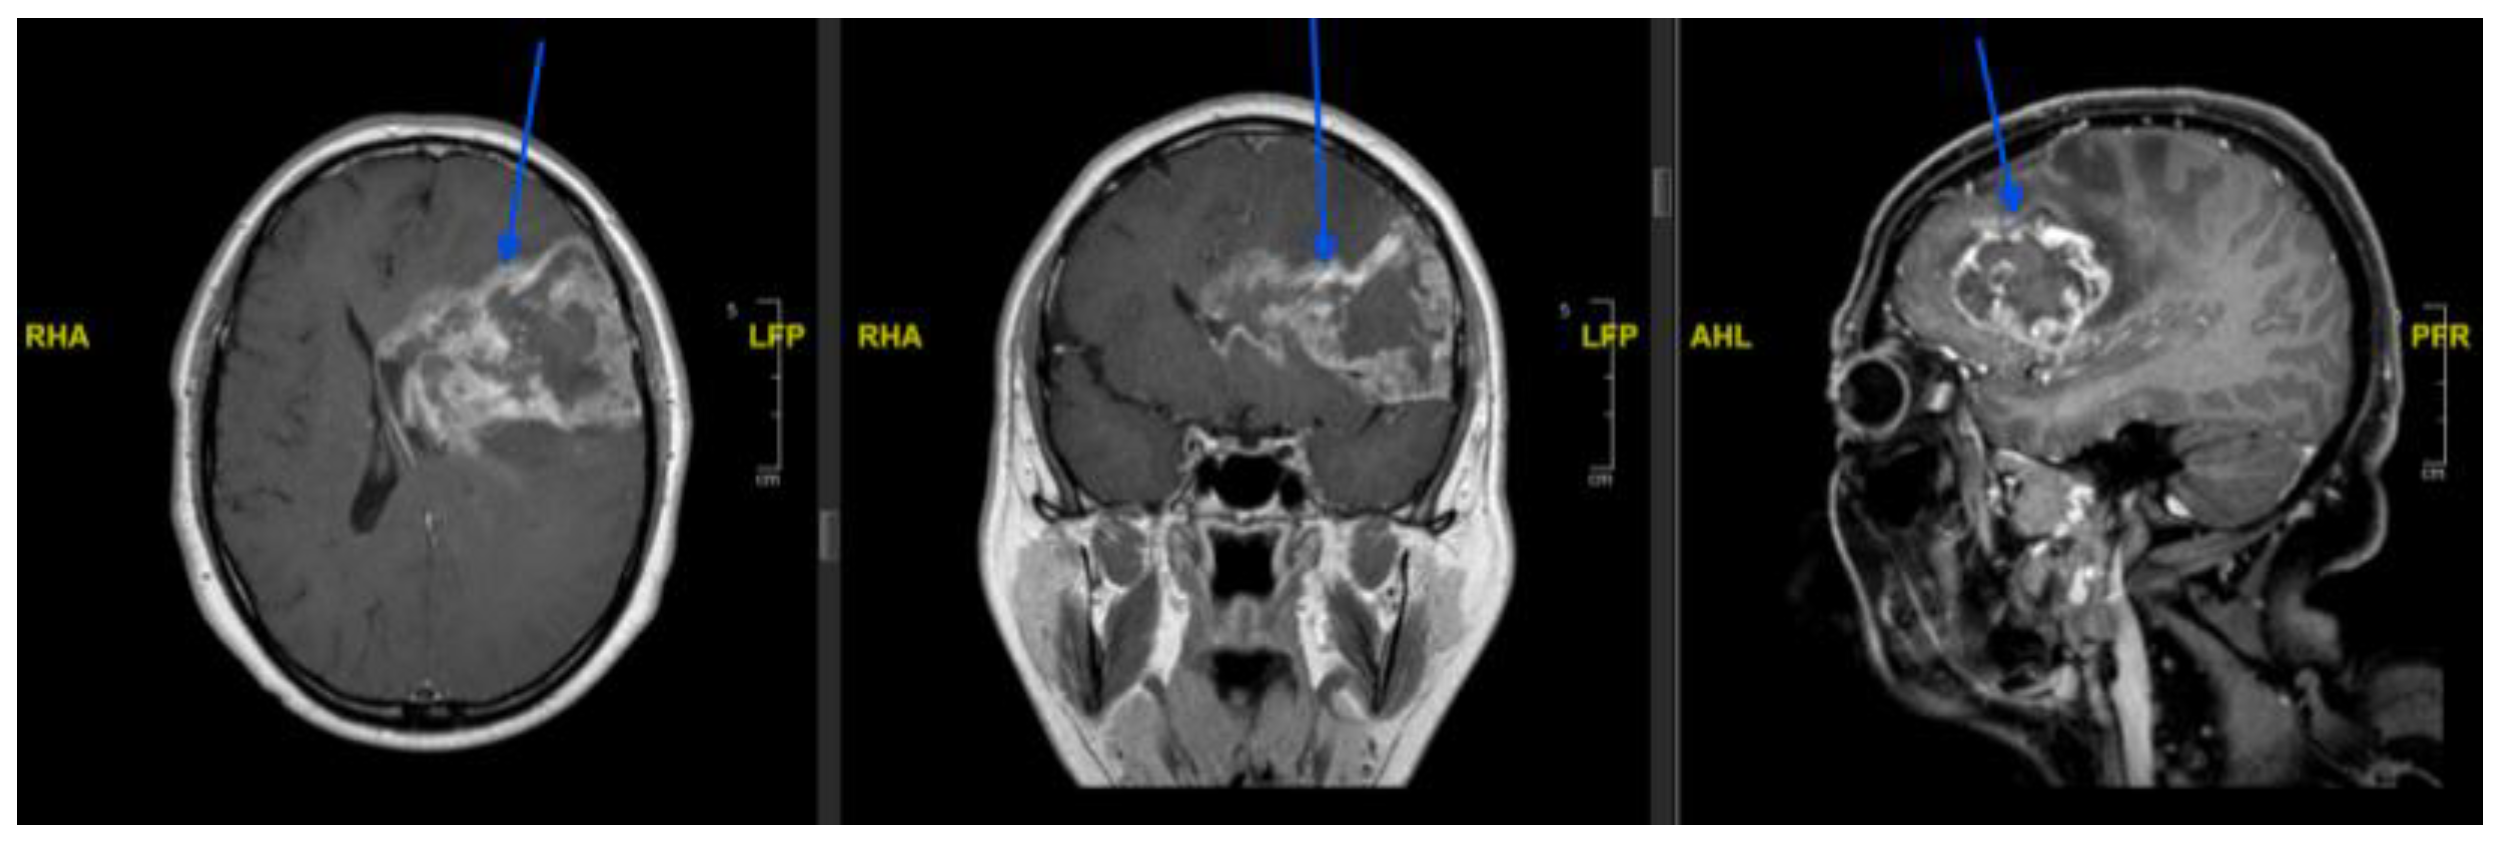

Background and Clinical Significance: Glioblastoma is the most common and aggressive primary malignant brain tumour in adults. Maximal safe surgical resection remains the cornerstone of treatment; however, tumour vascularisation may increase the risk of in-traoperative bleeding and complicate surgical management. Preoperative endovascular embolisation is commonly used for highly vascular intracranial tumours such as men-ingiomas, whereas its role in glioblastoma remains poorly defined. A focused literature review using the search string (((preoperative) AND (endovascular)) AND (embolization)) AND (glioblastoma) identified only two relevant publications, highlighting the scarcity of available evidence. In this context, we report a case series of three patients with intra-cranial lesions suspected to be high-grade gliomas who underwent preoperative angi-ographic evaluation and, when feasible, endovascular embolisation prior to surgical resection. Case Presentation: Three patients presenting with large intracranial lesions suggestive of high-grade glioma underwent preoperative digital subtraction angi-ography to assess tumour vascular supply (histological analysis confirmed the diagnosis of glioblastoma). In a 61-years-old woman with a right frontal tumour, selective catheteri-sation of a frontal branch of the right anterior cerebral artery enabled embolisation with coils, achieving partial tumour devascularisation before surgery. A second patient, a 53-year-old man with a large left temporo-fronto-insular mass extending to the corpus callosum, underwent embolisation of tumour feeders arising from the anterior choroidal artery using N-butyl cyanoacrylate and Lipiodol prior to resection. In a third case, a 77-year-old man with a left temporo-parietal lesion underwent preoperative angiography that demonstrated tumour capillary blush but no catheterisable feeding arteries, and embolisation was therefore not feasible. All patients subsequently underwent surgical resection without perioperative complications or new neurological deficits. Conclusions: Preoperative angiographic evaluation may help characterise tumour vascular supply in selected glioblastoma cases. When identifiable arterial feeders are present, endovascular embolisation may represent a feasible adjunct to facilitate surgical management. Further studies are required to better define the indications, safety profile, and potential benefits of this approach.